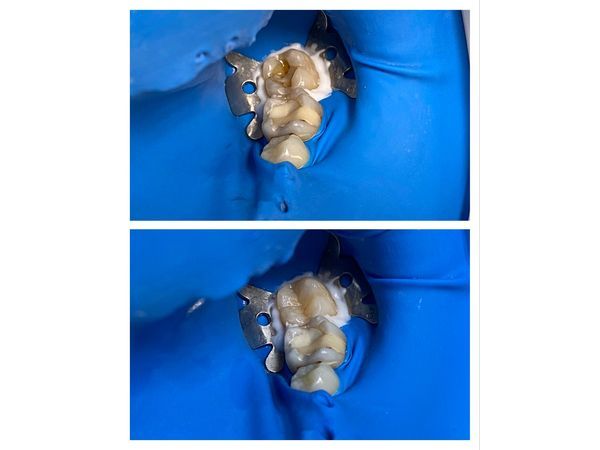

На зубе 3.7 дефект пломбы. Зондирование по дну кариозной полости болезненное, дентин дентин потемневший, размягчённый. Простукивание безболезненно, на холодное — кратковременная реакция. Часть дентина окрасилась кариес-детектором.

- ввели обезболивающее Ультракаин Д-С форте (1,7 мл) и изолировали зуб латексной завесой (коффердамом);

- сняли старую пломбу;

- препарировали кариозную полость с помощью стоматологических инструментов с воздушно-водяным охлаждением;

- нанесли кариес-детектор, чтобы убедиться, что все поражённые ткани убраны;

- сформировали полость зуба под композиционный материал;

- обработали зуб 37%-й ортофосфорной кислотой, чтобы зуб прочнее связался с пломбировочным материалом;

- провели адгезию (нанесли склеивающее вещество) и нанесли несколько слоёв светового композиционного материала, каждый слой засвечивая полимеризационой лампой;

- сформировали анатомические ориентиры зуба;

- проверили прикус с помощью артикуляционной бумаги, отшлифовали, отполировали щёткой и пастой.